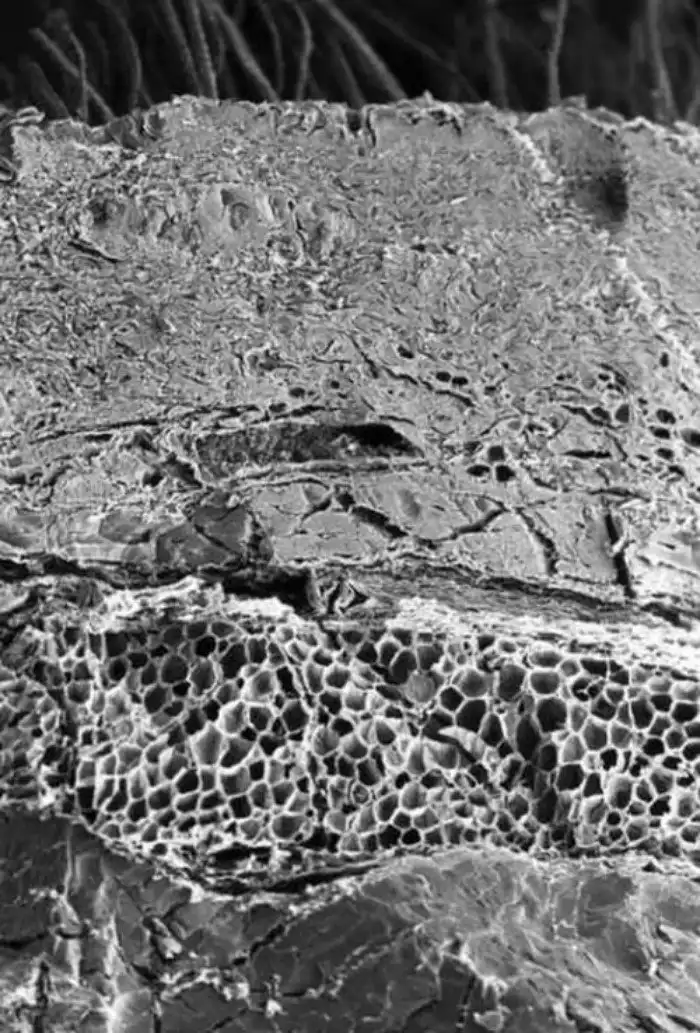

Кость